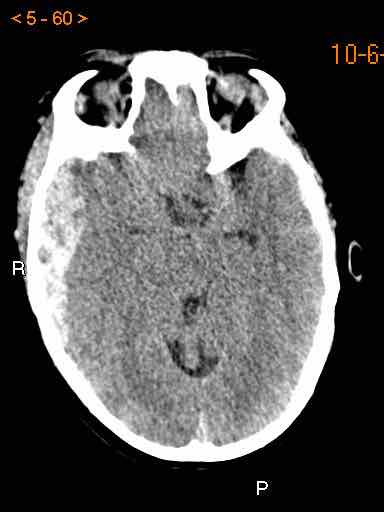

Bệnh nhân nam 46 tuổi bị chấn thương năng lượng cao khi đi xe máy.

Điểm EMV ban đầu là 2-5-3 và đồng tử hai bên giãn không phản xạ ánh sáng.

Hình ảnh CT

- Xuất huyết dạng chấm ở cả hai thùy trán.

- Gãy xương Le Fort II hai bên.

Tiếp tục xem các hình ảnh MRI…